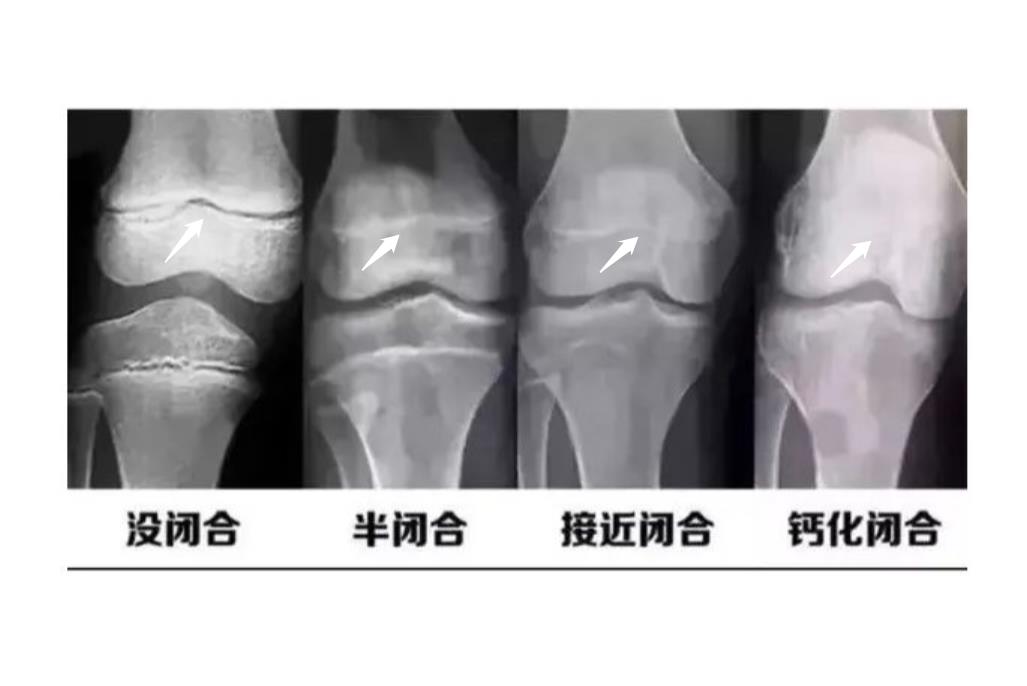

骨骺线是指长骨干骺端与骨骺之间的盘状软骨结构,该软骨成年后骨化与骨干和骺融为一体,留下的线叫做骨骺线。

骨骺线是指骨骺板的截面影像,骨骺与干骺端之间的软骨,在幼儿的x光片上表现为一条较宽的透光带。它随着年龄的增长而逐渐变短,当骨骺与干骺端的软骨完全骨化后,就形成一条紧密的缝,此时骨骺线完全闭合,长骨停止生长。长骨主要存在于四肢,当骨骺线完全闭合时,四肢就不继续生长。